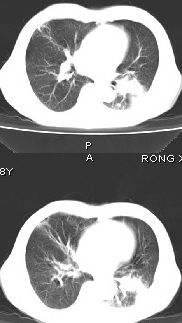

男68岁,反复发热、咳嗽,咯痰1月,曾有咯血史,双肺闻及呼吸音增粗。

左肺上叶尖后段及下叶多发实变阴影,内见支气管充气征,段以上支气管尚通畅,肺门区未见软组织肿块影,结合病人有反复发热病史,首先考虑感染性病变(干酪性肺炎不能排除),建议抗炎治疗后复查或结合纤支镜检查。

左肺上叶尖段及下叶干酪性肺炎可能性大,建议结合临床相关检查.右肺中叶炎症.建议治疗后复查.

该患者在25天前外圆平片见右肺中上肺野大片状影,(治疗不祥,在反复问病史后患者告诉;近一月住在新房内,搞装修),我认为首先考虑是感染,而且过敏性肺炎可能性大。